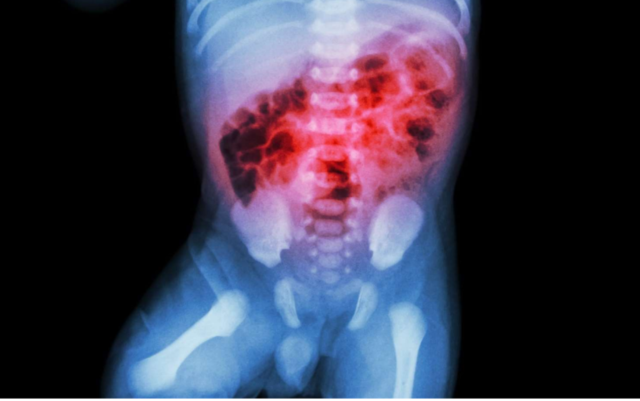

Casos de perforación intestinal "Hipótesis infecciosa"

• 62 casos de “Enteritis infecciosa severa”

• 85 casos de “necrotizing enterocolitis”

RN a término con historia de asfixia perinatal, 100% mortalidad, no encontraron agente infeccioso.

• 21-24 casos de EN por cada 1000 "Teoría multifactorial”:

Mortalidad 40.5%. Pico de 3 a 7 días.